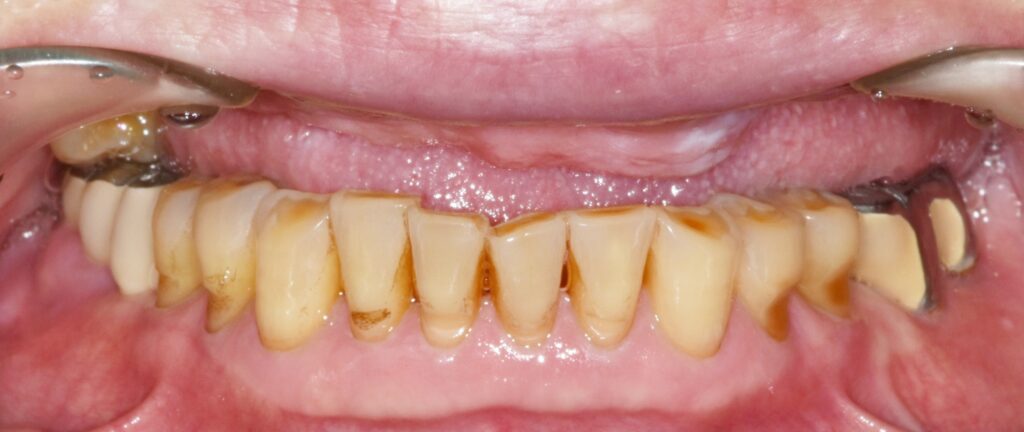

PMMA 임시보철로 적응 기간 갖는 이유

골유착이 완료된 후 임시치아를 써보는 기간

골유착이 완료된 이후에는 바로 최종 보철을 진행하지 않고, 👉 PMMA(임시 보철)를 일정 기간 사용하게 됩니다. 이 과정은 생각보다 매우 중요합니다.

을 충분히 검증해야 하기 때문입니다. 이번 환자분도 약 한 달간 PMMA 보철을 사용하면서 불편감이 없는지 꼼꼼히 확인하였습니다.